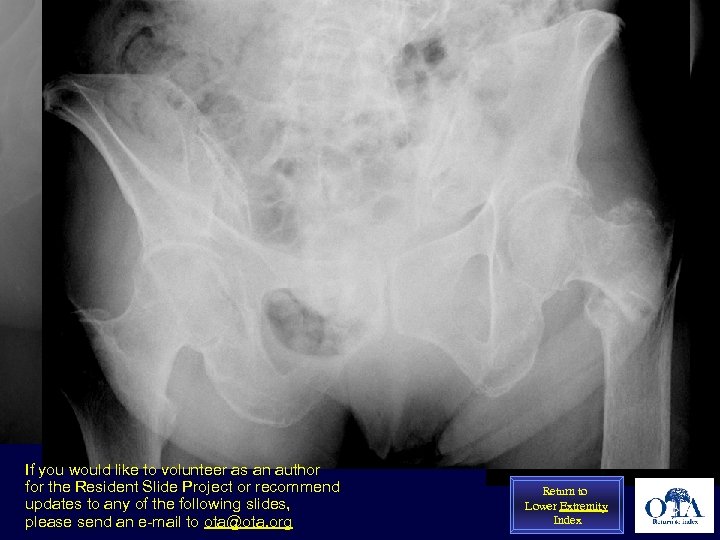

Uncontrolled factor: Bone quality A 33 year old pt with intertrochanteric fracture following a fall from height. Note the dense, cancellous bone throughout the proximal femur; Not at all like a geriatric fracture